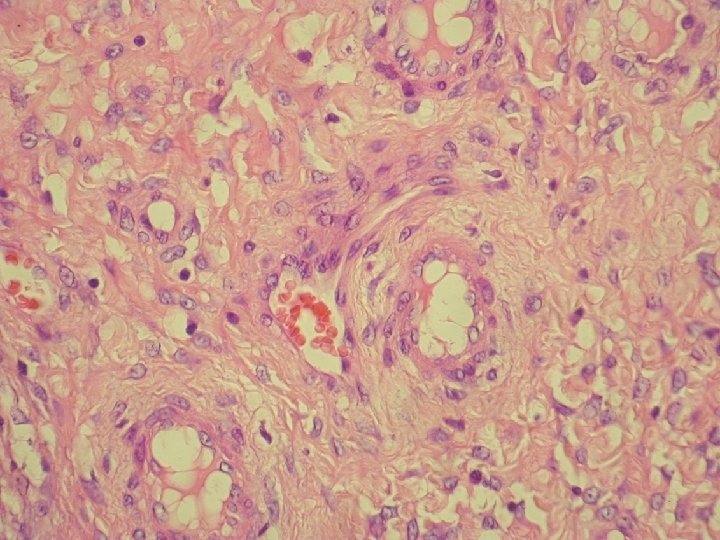

prolaps tuby asociovaný s exuberantnou angiomyofibroblastickou strómou

Klinicky: chronická abdominálna bolesť, dyspareunia polypoidné hemoragické masy Ø Histologicky: prezencia tubálneho epitelu s

Klinicky: chronická abdominálna bolesť, dyspareunia polypoidné hemoragické masy Ø Histologicky: prezencia tubálneho epitelu s variabilnou architektonikou v edematóznej, prevažne fibrotickej stróme Ø glandulárne prevažne tubálne inklúzie z malých epiteloidných buniek s eozinofilnou cytoplazmou, s riasinkami, sekretorické a „peg“ cells

Ø hladkosvalové vlákna a lymfoplazmocytárny infiltrát Ø bohatá vaskularizácia v retiformnej stróme, miestami aj

Ø hladkosvalové vlákna a lymfoplazmocytárny infiltrát Ø bohatá vaskularizácia v retiformnej stróme, miestami aj myxoidnej Ø Imuno: silná desmin pozit. Ø CD 34, S-100, alfa aktin, CK, calponin negat. Ø prezentovaná reaktívna stromálna proliferácia publikovaná v dvoch „case reportoch“